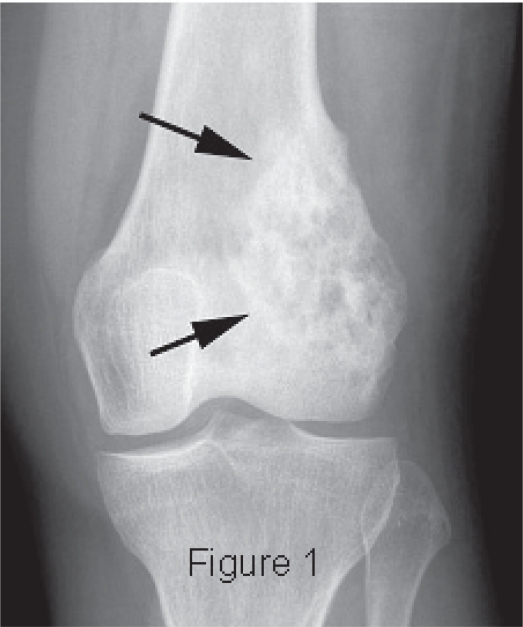

- Osteosarcoma: Osteosarcoma (sarcoma osteogenetico) è il secondo più comune tumore maligno dell'osso. È più comune tra individui che vanno dai 10 ai 25 anni di età, sebbene che possa capitare a tutte le età. L'Osteosarcoma produce osteoidi maligni (osso immaturo). Solitamente si sviluppa intorno al ginocchio (femore distale più frequente di quello prossimale di tibia) o in altre ossa lunghe, specialmente in regione metafiso-diafisaria e può metastatizzare, solitamente al polmone o ad altre ossa [4]. Il dolore e il gonfiore locale sono i sintomi usuali.

- Tumore giganto-cellulare maligno: È un tumore raro e si colloca alle estremità delle ossa lunghe. Le radiografie mostrano il tipico aspetto della distruzione ossea (prevalentemente lisi ossea, distruzione corticale, estensione ai tessuti molli e fratture patologiche). Il trattamento è simile a quello per l'osteosarcoma, ma le guarigioni sono rare.

- Aspetto litico, distruttivo

- Bordi irregolari del tumore

- Aree di distruzione ossea

- Distruzione delle corticali

- Invasione dei tessuti soffici circostanti

- Fratture patologiche